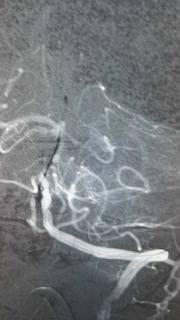

术中见患者基底动脉上段闭塞,典型的基底动脉尖综合征。基底动脉尖综合征是一种潜在的致命性神经系统疾病,进展极快,临床医生诊断和治疗该病面临很大挑战,其约占所有缺血性卒中的 1%-4%,死亡率更是高达75%。

术中结果不容乐观,如果基底动脉闭塞不处理,患者随时可能出现中枢性呼吸循环衰竭导致死亡。

目前最适合的救治办法是短时间内取出血栓,方能恢复脑血管血供,恢复患者神经功能。

脑动脉机械取栓术听起来简单,但操作起来难度颇大。其操作方法是:股动脉穿刺置入一根细细的导管,缓慢上行至脑血管,精确定位后再次置入一个取栓导丝,释放导丝,让导丝包裹血栓,再像拔红酒瓶塞一样回收导丝,取出血栓。

手术要求的精细度极高,对操作者的技术水平、熟练程度、心理素质、团队协作等都是极大的考验。江顺福主任都是有着多年血管介入临床经验的介入专家,血管内技术炉火纯青;吴明超副主任医师则刚刚从南京学了脑动脉取栓技术回到神经内科,对脑梗塞的治疗相当娴熟。两位专家充分运用纯熟的血管介入技术,密切配合,终于顺利取出了盘居在脑动脉内的“夺命血块”。经过1个多小时的紧张手术后,成功取出栓子,患者闭塞的基底动脉开通,术后安返病房严密监测及术后的继续治疗。术后24小时患者神志转清,能回答问题,家属非常感动。